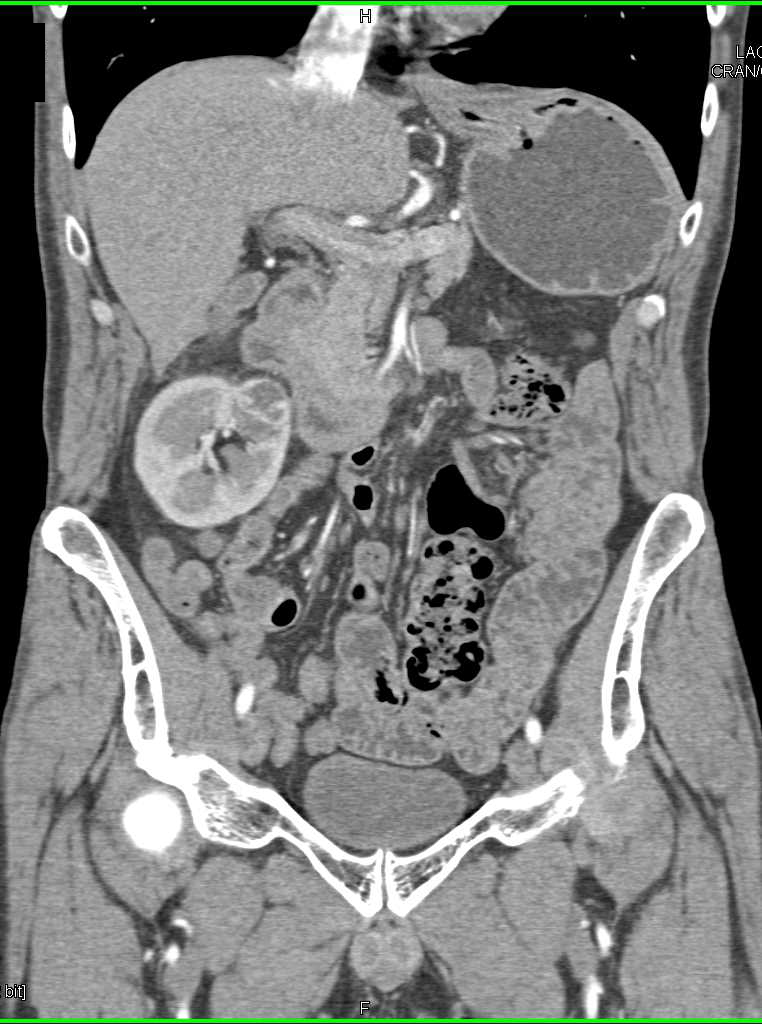

2 cm Right Renal Cell Carcinoma